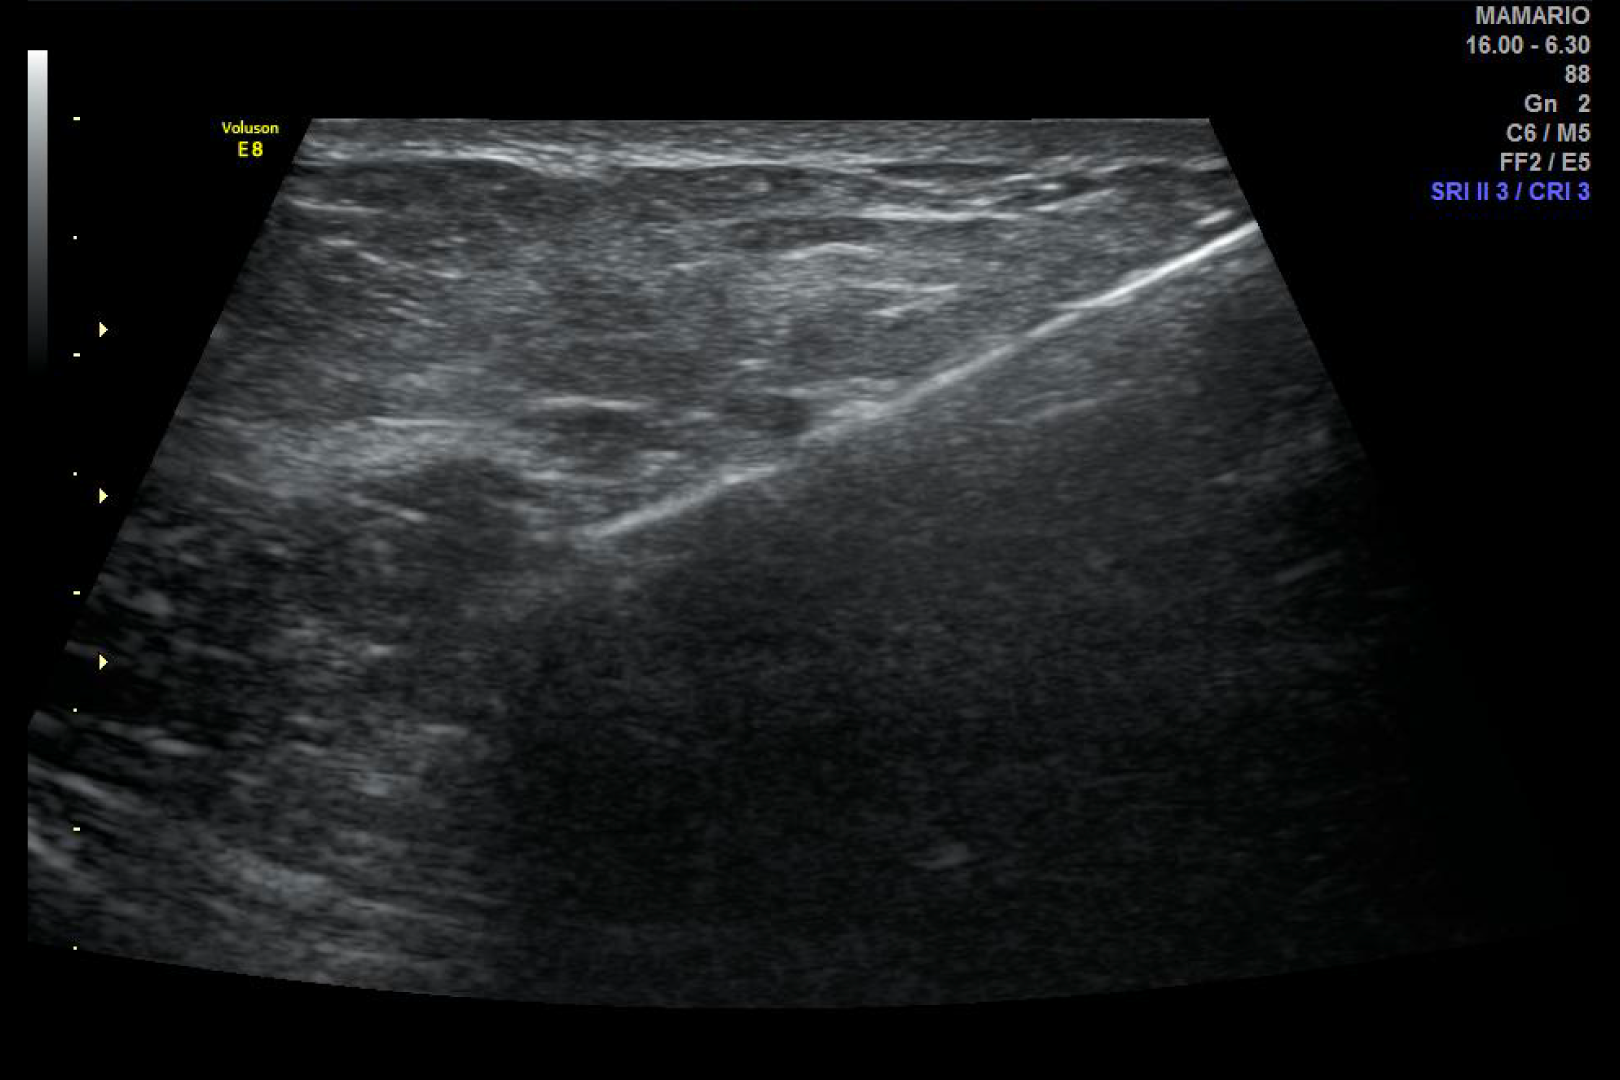

HD Live quinta dimensión, Imágenes de volumen con profundidad y claridad, que aportan un realismo anatómico para un mejor diagnóstico.